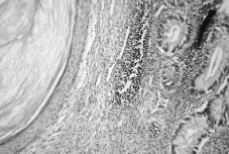

El informe anatomopatológico de la pieza fue de teratoma maduro intrauterino con áreas de diferenciación linfoide, intestinal y pulmonar. (Figs. 1, 2 y 3).

Figura 1. Detalle del teratoma conteniendo epitelio escamoso y epitelio intestinal.

Figura 2. Ampliacion de la figura 1.